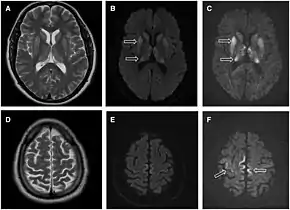

Magnetic resonance image of sporadic CJD[2]

Through the image of MRI, the obvious precipitation of prion protein in the brain is visible.

• MRI of the brain – often shows high signal intensity in the caudate nucleus and putamen bilaterally on T2-weighted images.

Imaging of the brain may be performed during medical evaluation, both to rule out other causes and to obtain supportive evidence for diagnosis. Imaging findings are variable in their appearance, and also variable in sensitivity and specificity.[43] While imaging plays a lesser role in diagnosis of CJD,[44] characteristic findings on brain MRI in some cases may precede onset of clinical manifestations.[45]

Brain MRI is the most useful imaging modality for changes related to CJD. Of the MRI sequences, diffuse-weighted imaging sequences are most sensitive.[46] Characteristic findings are as follows:

• Focal or diffuse diffusion-restriction involving the cerebral cortex and/or basal ganglia. In about 24% of cases DWI shows only cortical hyperintensity; in 68%, cortical and subcortical abnormalities; and in 5%, only subcortical anomalies.[47] The most iconic and striking cortical abnormality has been called "cortical ribboning" or "cortical ribbon sign" due to hyperintensities resembling ribbons appearing in the cortex on MRI.[48] The involvement of the thalamus can be found in sCJD, is even stronger and constant in vCJD.[49]

• Varying degree of symmetric T2 hyperintense signal changes in the basal ganglia (i.e., caudate and putamen), and to a lesser extent globus pallidus and occipital cortex.[44]